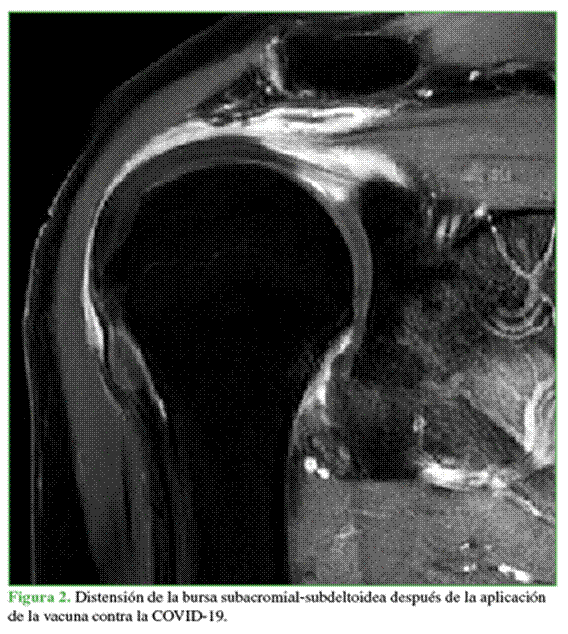

Las LHAV se presentan más comúnmente con bursitis subacromial y subdeltoidea,4-6,8,9-15 y lesiones del manguito rotador.4,5,8,13,15 En cuanto a los tendones más afectados, se han comunicado lesiones en el supraespinoso, subescapular, infraespinoso y redondo menor.13,14 Szari y cols.10 describieron un caso de LHAV con imágenes por resonancia magnética de tendinopatía en los cuatro tendones del manguito rotador y posible tendinopatía calcificante del redondo menor.

Los hallazgos iniciales denotan cambios inflamatorios en partes blandas. Es frecuente detectar un aumento del líquido dentro de la bursa subacromial/subdeltoidea en la ecografía y la resonancia magnética (Figura 2). Salmon y cols.22 compararon estas imágenes iniciales con las diferidas a los cinco meses y observaron una regresión del derrame articular y una disminución de la bursitis, por lo que estos estudios pueden no ser muy demostrativos en cuadros crónicos.14

Lo primero que hay que descartar es un cuadro séptico. Distinguir la bursitis infecciosa de la relacionada con la vacuna es particularmente difícil en las imágenes por sí solas. Si bien es muy probable que las radiografías del hombro tengan una apariencia normal, puede haber irregularidad cortical del húmero.23 En la resonancia magnética, la bursa llena de líquido aparecerá hiperintensa en la secuencia T2. En la ecografía, se observará como una estructura anecoica llena de líquido rodeada de paredes hiperecoicas.23 En estos casos, la historia clínica y los resultados de los análisis de laboratorio son los elementos más útiles para distinguir estas etiologías.